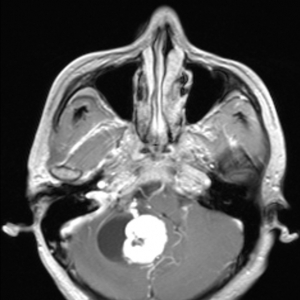

2014年10月9日,AJNR杂志刊登了如下一则病例报道。患者男性,47岁,顽固性头痛、头晕、和不平衡感。图1. 增强的水平位头颅MRI T1像显示右侧小脑内一囊肿,囊肿内包含一个紧贴一侧囊壁的高信号结节。图2、3. 增强的失 ...